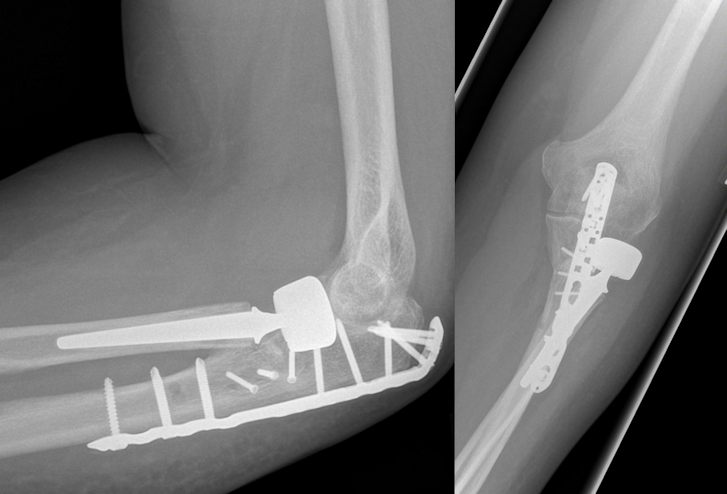

Osteosynthesis of the ulna was performed using a proximally contoured 3.5 mm LCP (locking compression plate) or precontoured 3.5 mm LCP Olecranon Plate (both Synthes GmbH, Umkirch, Germany) applied to the posterior surface of the ulna in dynamic compression mode (Figure 1 [Fig. 1], Figure 2 [Fig. 2], Figure 3 [Fig. 3]).

Figure 1: Male patient (43 years) with a posterior Monteggia-like lesion (Bado type II, Jupiter type IIB), Mason type III fracture of the radial head, and Broberg and Morrey type III coronoid fracture. Radiographs on the day of the injury.

Figure 2: Postoperative radiographs. Osteosynthesis of the ulna was performed using a proximally precontoured olecranon plate applied to the posterior surface of the ulna. Implantation of a cemented bipolar radial head prosthesis.

Figure 3: Same patient 11 months after the injury: no degenerative changes and heterotopic ossifications. No signs of loosening of the radial head prosthesis. Good clinical outcome.